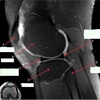

1

Not at all

2

3

4

5

Perfectly

11

Q

What is letter A?

A

ANTERIOR LABRUM

How well did you know this?